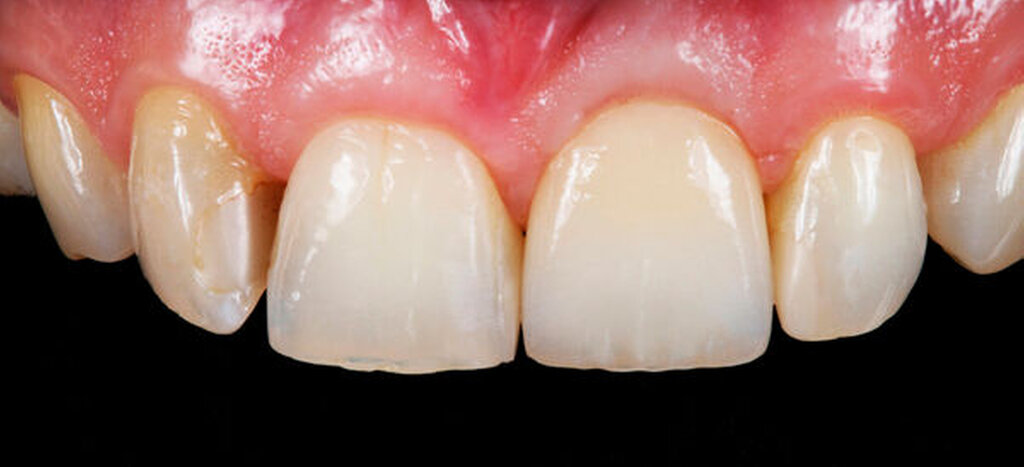

Im vorliegenden Patientenfall wurde sich bereits im Zuge der Implantatplanung (siehe auch den Abschnitt „Implantatpositionierung“) für eine transokklusal verschraubte Krone entschieden. Die Implantatkrone wurde im Hybridverfahren aus Lithiumdisilikat und der zugehörigen Titanklebebasis gefertigt (Abbildung 7). Entsprechend der Vorgabe des Implantatherstellers wurde die Krone mit einem Drehmoment von 20 Ncm eingeschraubt. Zu beachten ist, dass das Drehmoment sich zwischen den Herstellern und Implantattypen, aber auch den verwendeten Materialien des Dentallabors unterscheiden kann. Der transokklusale Schraubenkanal wurde abschließend mit Teflonband und Komposit verschlossen (Abbildungen 8 und 9). Bei auf Implantatabutments zementierten Kronen kann der Hohlraum zwischen der provisorischen Abdeckung des Schraubenkopfes und der definitiven Krone auch als Abflussreservoir für den Befestigungszement dienen. Hier entfällt der okklusale Verschluss mit Komposit.

Bei Beachtung der diskutierten Arbeitsschritte und der möglichen Fehlerquellen kann die implantologische Versorgung der Einzelzahnlücke eine langfristig erfolgreiche Therapie darstellen, die für jeden implantologisch interessierten Zahnarzt umsetzbar ist. Dabei sollten die individuellen therapeutischen Grenzen stets bekannt sein. Die implantatprothetische Rehabilitation im Frontzahnbereich wird dabei häufig als „Königsdisziplin“ beschrieben. Auch diese ist jedoch unter Berücksichtigung aller Parameter hochästhetisch möglich (Abbildungen 10 bis 12).